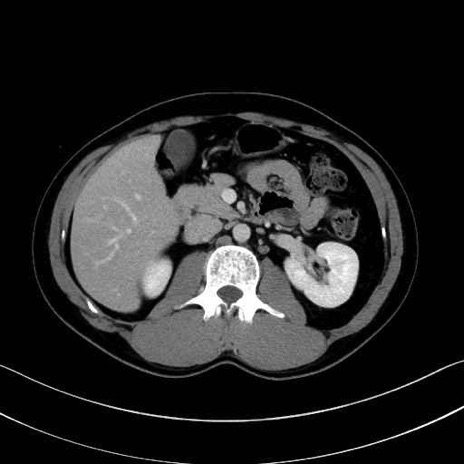

【症例】20歳代 男性 スクリーニング

■起始:典型的には腹腔動脈幹(celiac trunk)から左胃動脈・総肝動脈とともに三分岐し、脾動脈は左後上方へ向かう。

■走行:膵上縁または膵実質背側を蛇行しながら左方へ進み、膵尾部近傍で脾門へ至る。蛇行の程度は個体差が大きい。

■終枝:脾門部で複数の終末枝に分かれ、上極・下極枝や脾門枝群を形成する。胃短動脈群や左胃大網動脈はしばしば脾動脈から分岐する。